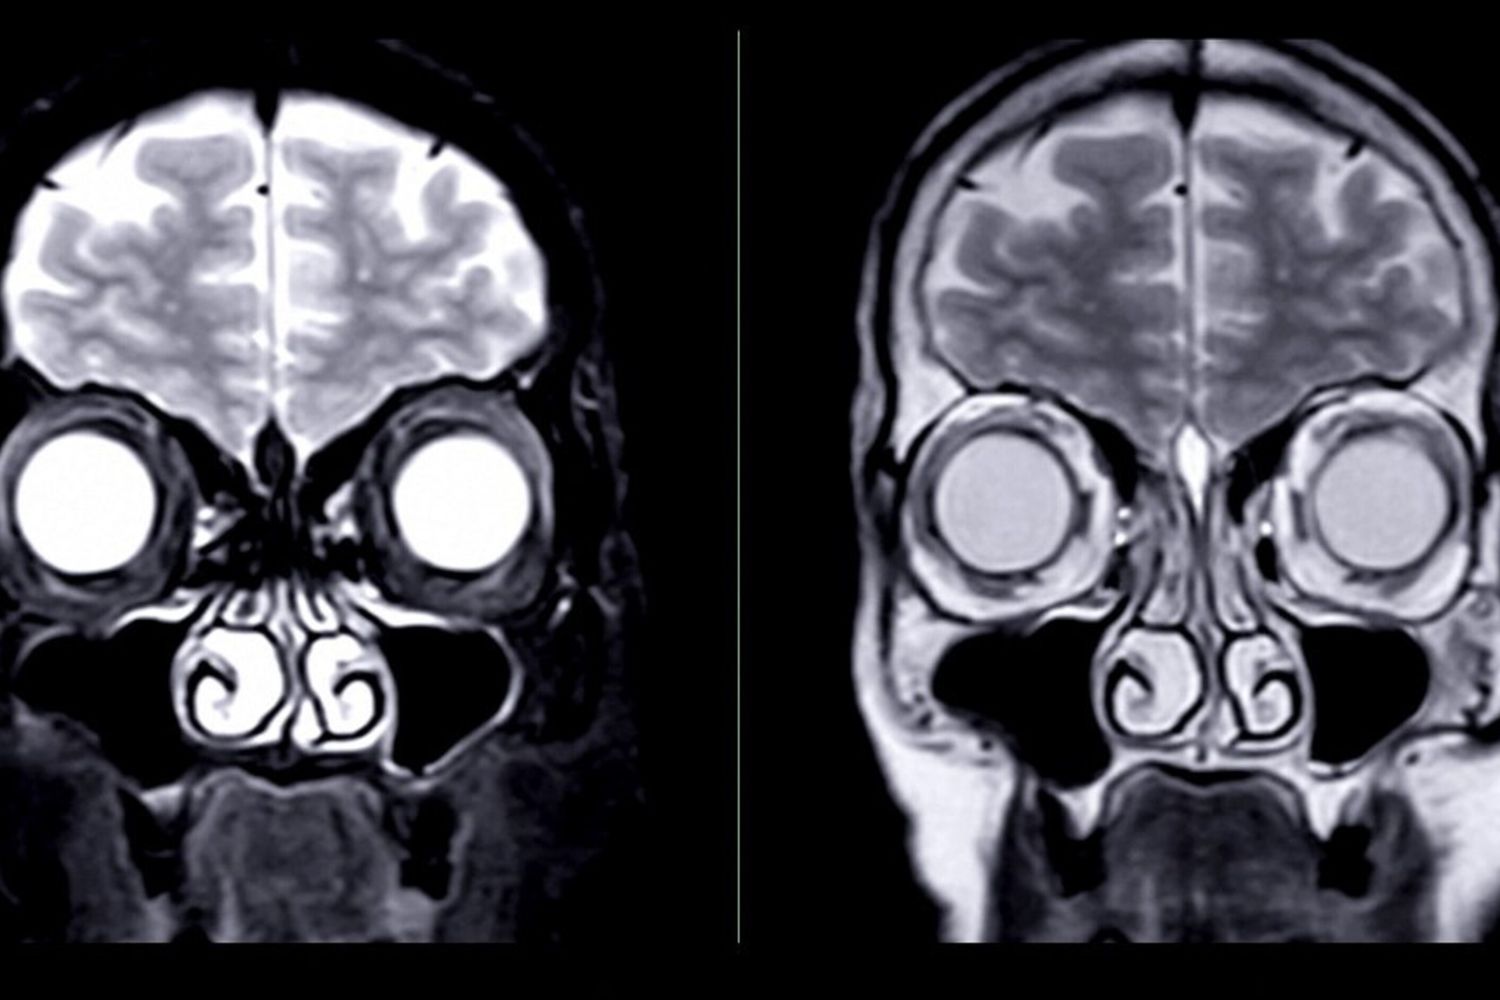

Un'analisi del Collaboration Linking Opioid Use Disorder and Sleep Study (Clouds), finanziata dai National Institutes of Health, ha messo a confronto tra febbraio 2021 e maggio 2023 persone con disturbo da uso di oppioidi in trattamento con metadone e i controlli sani, tramite una risonanza magnetica strutturale e una risonanza magnetica funzionale (fMRI) a riposo, utile a misurare l'attività cerebrale, cioè la connettività tra le regioni neurali, note come reti a riposo, rilevando alcuni cambiamenti nel flusso sanguigno.

L'analisi si è basata su 103 risonanze magnetiche strutturale Clouds di individui con disturbo da uso di oppioidi e 105 controllo e su 74 fMRI a riposo di partecipanti con disturbo da uso di oppioidi e 100 controlli. Gli individui con disturbo da uso di oppioidi erano stabilizzati con farmaci per il disturbo, assunti da meno di 24 settimane. L’Età media nel gruppo con disturbo da uso di oppioidi era di 37 anni, con il 40% erano donne, contro una età media di 27 anni e 55% di donne nel gruppo di controllo.

L'analisi dell'intero cervello ha rivelato alterazioni strutturali e funzionali nelle regioni dense di recettori degli oppioidi nel gruppo con disturbo da uso di oppioidi rispetto ai controlli sani, tra cui dimensioni inferiori del talamo e del lobo temporale mediale destro del cervello e dimensioni aumentate di cervelletto e tronco encefalico. "Inoltre, negli individui con disturbo da uso di oppioidi, abbiamo osservato aumenti diffusi nella connettività globale", ha affermato Saloni Mehta, del Dipartimento di radiologia e imaging biomedico della Yale School of Medicine.